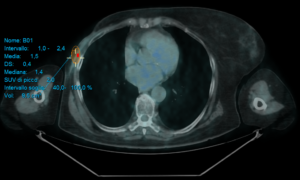

L’assorbimento del radiofarmaco osteotropo nelle aree di rinnovamento osseo e nelle lesioni con attivazione osteoblastica dipende non solo dall’entità di tale attivazione, ma anche dall’aumento del flusso sanguigno regionale.

Dopo l’iniezione endovenosa, il radiofarmaco si diffonde rapidamente nello spazio extracellulare, e l’assorbimento da parte del tessuto osseo inizia immediatamente. La quantità di attività ancora presente nel circolo sanguigno 30 minuti dopo l’iniezione è approssimativamente il 10% di quella iniziale, diminuendo gradualmente fino a raggiungere circa l’1% dopo circa 4 ore dalla somministrazione. L’eliminazione avviene principalmente attraverso i reni, con circa il 50-60% del radiofarmaco che viene escreto intatto nelle prime 6 ore dall’iniezione.